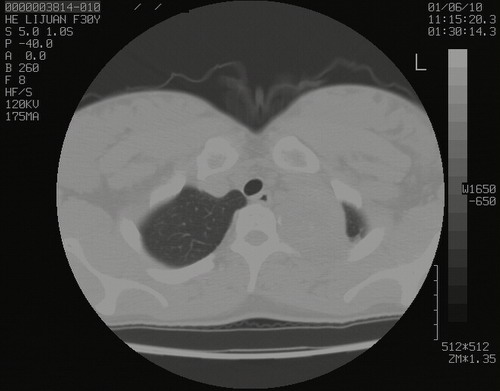

怀孕3个月时(2009-3至4月间),自述突感左侧前后胸疼痛1天,以前胸明显,随后偶感闷痛,余未见异

左肺尖脊柱旁沟肿块,境界清楚,边缘光滑,密度不均,内有多发点片状钙化,考虑良性肿瘤,骨软骨瘤或神经源性肿瘤可能,肺错构瘤不除外。

左后上纵隔见一类圆形肿块影,外侧边界清,密度不均匀,内可见点状钙化影,增强呈不均匀强化,考虑神经源性肿瘤可能。期待病理结果。